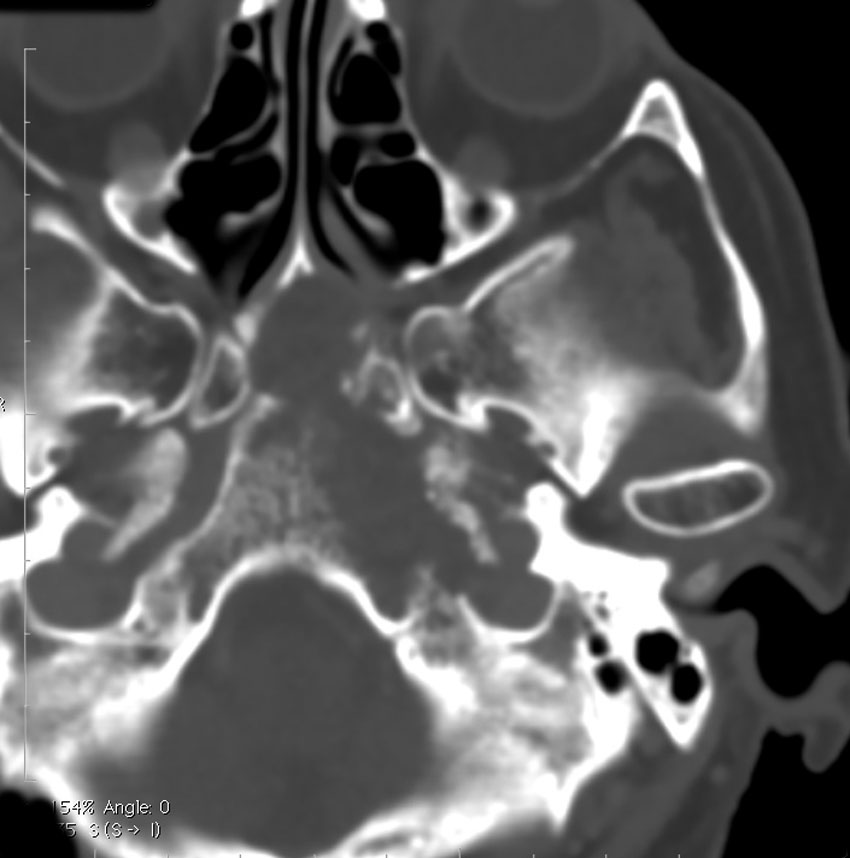

CTでは腫瘍実質部分が増強されます。不規則な骨破壊像・浸食像が特徴的です。

骨軟骨腫が若い時からあって壮年になってから悪性化した軟骨肉腫です。20代のときに右外転神経麻痺が生じて20年以上そのまま経過しました。左のCTでは頭蓋骨の真ん中の斜台というところに異常な骨があって,良性の骨軟骨腫のように見えます。でも右側のMRIでは脳幹部に深く食い込む柔らかい腫瘍の部分が写っていてこれは軟骨肉腫を疑う像です。手術摘出と術後の放射線治療をしました。